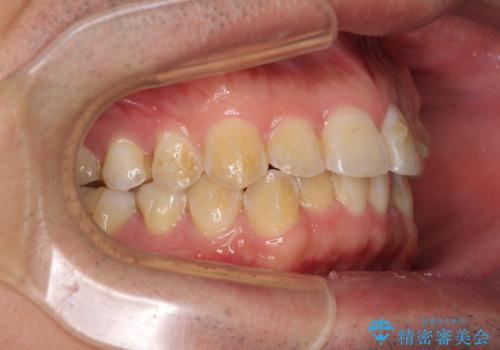

ディープバイトと叢生を解消 インビザライン矯正

- 前歯のデコボコを強い咬みしめを気にして来院された患者様です。

インビザラインを用いて、前歯の叢生を解消するとともに、ディープバイトを改善していくこととしました。

ディープバイトが改善されたことで、顎への負担が軽減され、更には上顎前歯の突出感も改善することができました。

矯正治療後には欠けてしまった修復物をセラミックインレーにて修復治療しました。